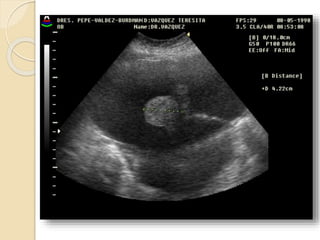

Quistes Endometrósicos:

Clínicamente se manifiesta por dismenorrea,

dispareunia e infertilidad.

La lesion mas detectable por la imágenes esta

constituida por los quistes endometrosicós

(endometriomas) que se forman a partir de los

implantes ováricos configurando los quistes

“achocolatados”.

Se observan quistes de paredes relativamente

gruesas e irregulares con débiles ecos en su

interior debido al contenido hemático.